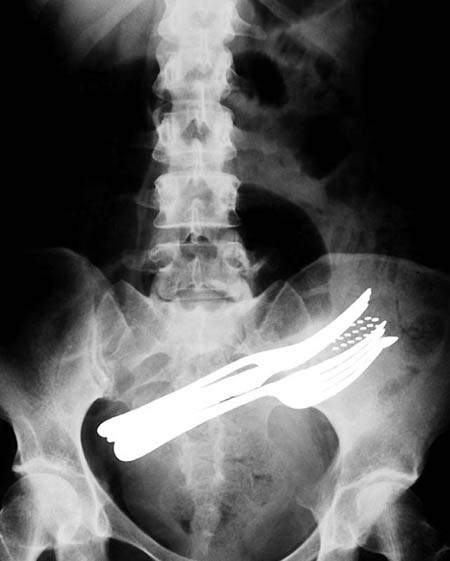

嚥下筆、牙刷和2隻叉的胃